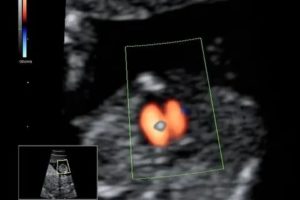

На ультразвуковом исследовании ГЭФ выглядит на мониторе как маленькая белая точка в районе сердца, обычно в левом желудочке. Если снимок увеличить в несколько раз, станет хорошо заметно овально-круглое образование, слегка перемещающееся при каждом биении сердца.

На УЗИ ГЭФ виден в виде гиперэхогенных “горошин”

Частота встречаемости – около 7%. Гэф в желудочках сердца плода – это маленькое образование внутри полости сердца, которое при проведении УЗИ по эхоструктуре сравнимо с костной тканью. К основным УЗ критериям патологии относятся:

- Размер от 1 до 6 мм;

- Месторасположение – на папиллярной сердечной мышце или на сухожильной хорде;

- Чаще всего выявляется в левом желудочке (94% случаев);

- Не дает специфической звуковой тени при проведении УЗИ;

- Двигается синхронно с сердечными клапанами.

На ультразвуковом исследовании врач видит яркое белое пятно в пределах 2-3 мм округлой формы в полости одной из камер сердца плода.

Ультразвуковые диагносты очень любят всяческие художественные сравнения, поэтому гиперэхогенный фокус также носит название golf ball или симптом гольфного мяча.

На самом деле, небольшое округлое образование, подпрыгивающее при каждом сокращении сердца, действительно напоминает мячик для гольфа.

Дать такую картину на УЗИ может лишь очень плотное образование сродни костной ткани, что и вызывает некоторое удивление всех ученых и врачей. Каким образом такое плотное образование формируется в сердечной мышце, а потом бесследно пропадает после рождения – остается неразгаданной загадкой.